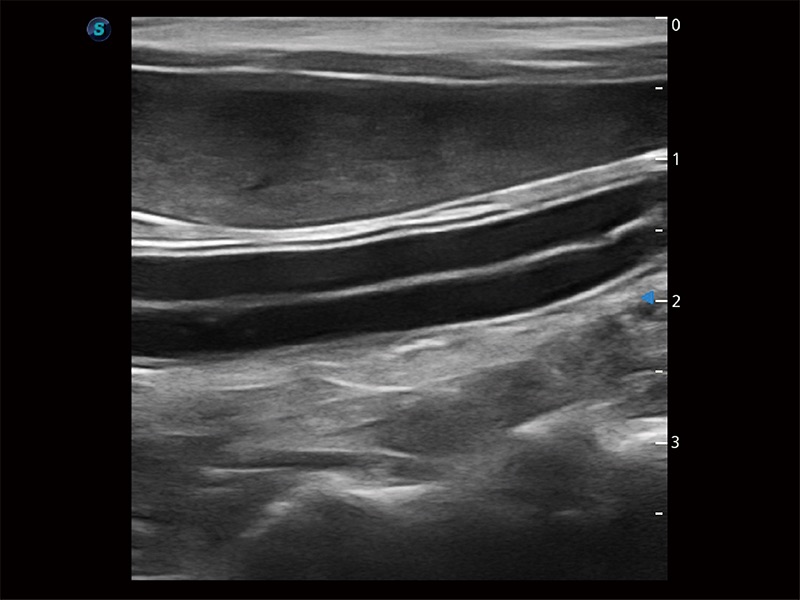

高性能和先进的临床应用工具可以为动物医生提供临床信心。ProPet 80 搭载了先进的腹部和浅表应用工具,帮助医生在日常临床实践中发挥前所未有的作用。

极大提升超低速微细血流的检出能力,同时更精准地滤除软组织和超声信号,为兽用医生提供以往无法通过常规血流获得的疾病诊断信息。

操作简便,无需高频度外力作用即可真实反映组织的形变,快速评估肿瘤良恶性。

为精细结构及组织边缘提供高清晰度的图像和更大的成像视野。帮助减轻医生的用眼疲劳,快速精准获得测量的数据。